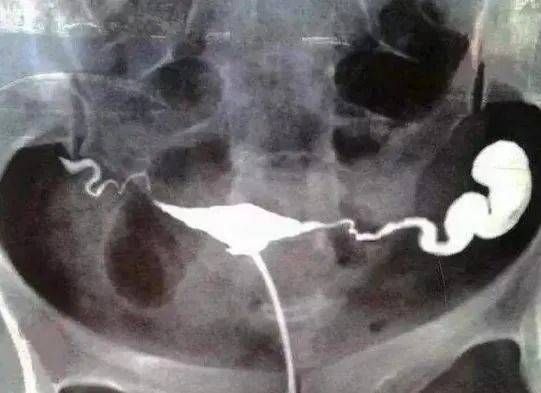

卵管积水是慢性输卵管炎症中比较常见的类型,大多数输卵管积水是由局部炎症引起,比如分娩、流产、不洁性生活或不注意经期卫生以及妇科手术后发生炎症而导致。如果邻近脏器发生炎症,如阑尾炎,腹膜炎等也会殃及输卵管。输卵管发生炎症以后,因为粘连、闭锁,黏膜细胞的分泌液积存于管腔内,发生伞端和峽部的粘连、阻塞而形成输卵管的积水的发生。

输卵管积水主要临床表现是离经期越近,疼痛感就会越严重,大多下腹一侧或两侧有疼痛感,直到月经的来潮。有时表现为月经过多或者月经频发,往往伴有不孕。

严重的输卵管积水可使输卵管正常功能完全丧失,输卵管积水的治疗最终目的是尽量的恢复输卵管的解剖和生理功能,如果不能恢复它的解剖和生理功能,又有生育的要求,就需要做输卵管的切除术。因为输卵管积液主要是含有大量的的白细胞等炎性因子,是造成胚胎着床障碍、早期流产的重要因素。即使做试管婴儿,严重的输卵管积水也会导致移植失败。